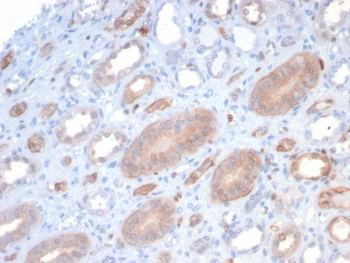

Cathepsin D Antibody

| Description | Cathepsin D Antibody |

| Tested applications | FC, ICC, IHC, IP, WB |

| Reactivity | Human, Mouse |